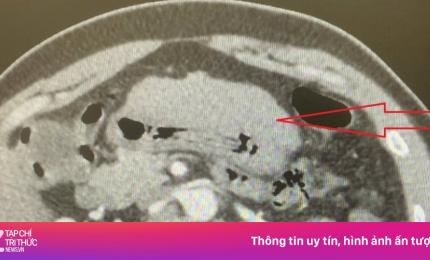

Nam bệnh nhân 35 tuổi bất ngờ phát hiện suýt vỡ gan từ cơn đau bụng